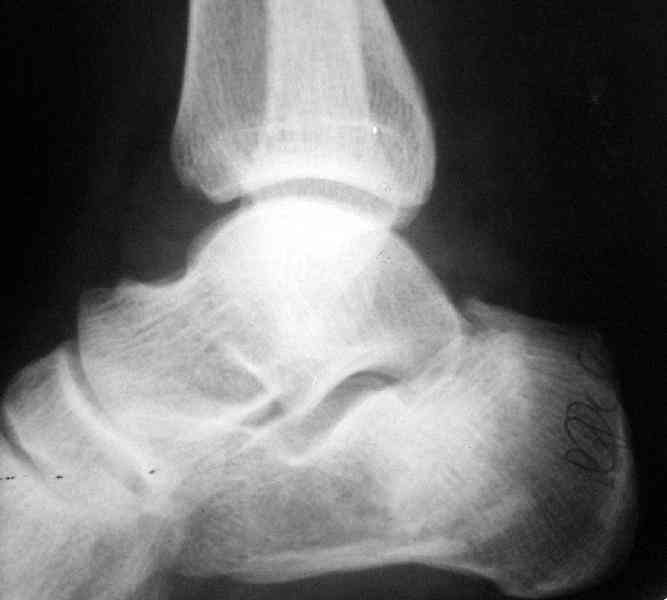

Re: Перелом пяточной кости

Открытый и закрытый способы лечения.